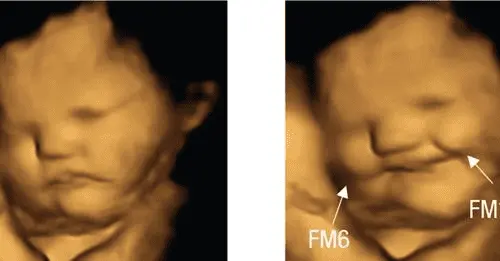

Images from fetuses in the womb show they smiled after their mothers ate carrots but scowled over kale, a new study released this week shows.

"Findings of this study have important implications for understanding the earliest evidence for fetal abilities to sense and discriminate different flavors," researchers wrote in study findings released Wednesday.

According to the recent study of 99 pregnant women and their fetuses in England, researchers gave the mom's capsules containing powdered versions of the two foods.